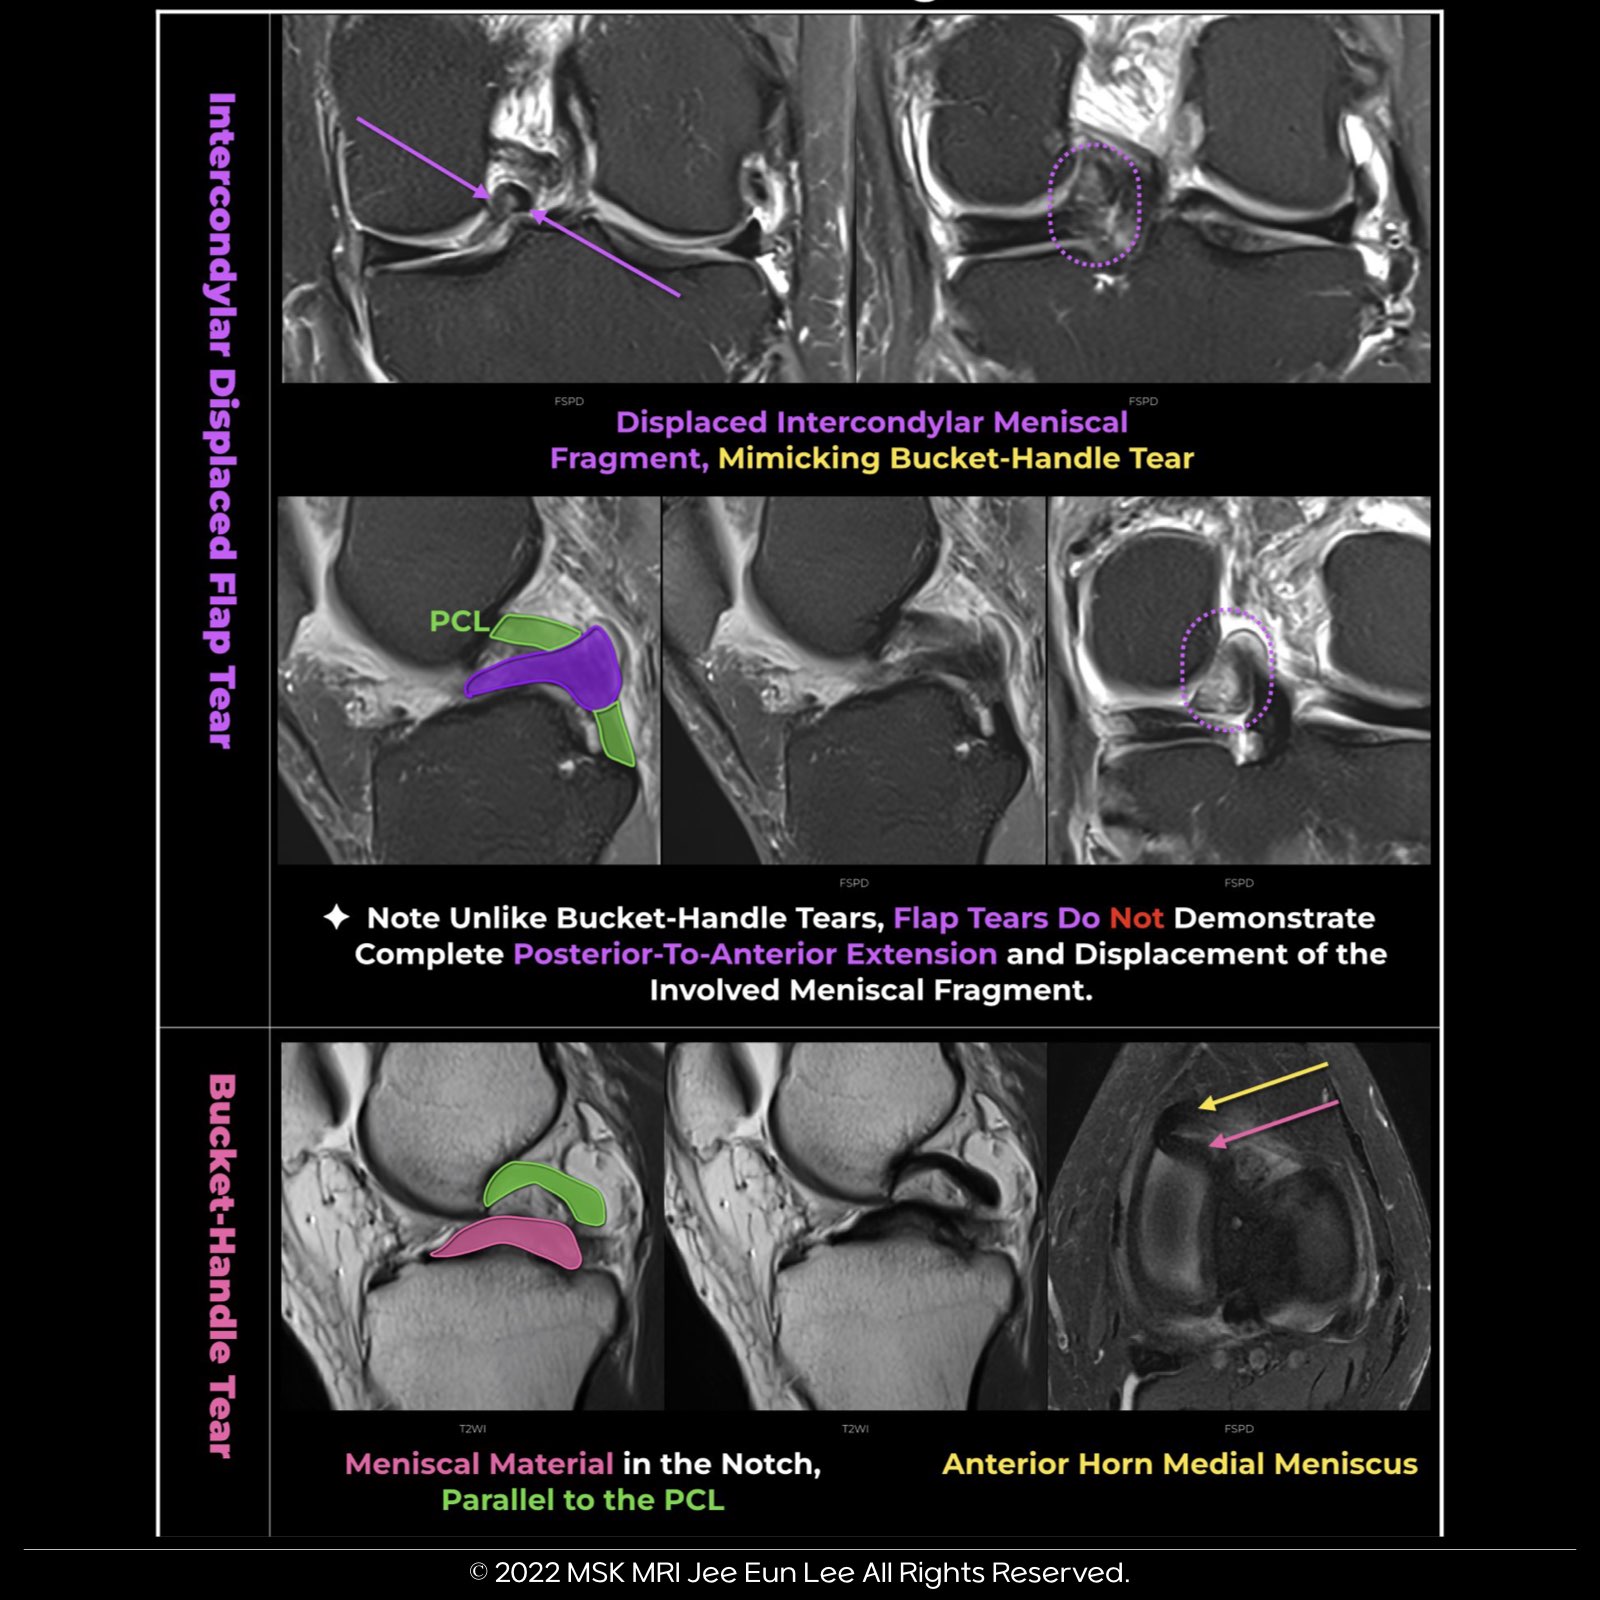

Flap Tear vs. Bucket-Handle Tear:

- Flap tears, unlike bucket-handle tears, do not show complete posterior-to-anterior extension and displacement of the involved meniscal fragment. In this scenario, the flap tear mimics a bucket-handle tear, yet distinct differences are evident upon closer examination.

The Double Posterior Cruciate Ligament (PCL) Sign:

- This sign results from meniscal material in the notch, inferior and parallel to the PCL in the same sagittal plane.

- The displaced fragment, in proximity and posterior to the anterior horn segment, contributes to this sign.

The Anterior and Posterior Triangles:

- In this context, the anterior triangle represents the normal anterior horn, while the posterior triangle symbolizes the displaced bucket handle segment.